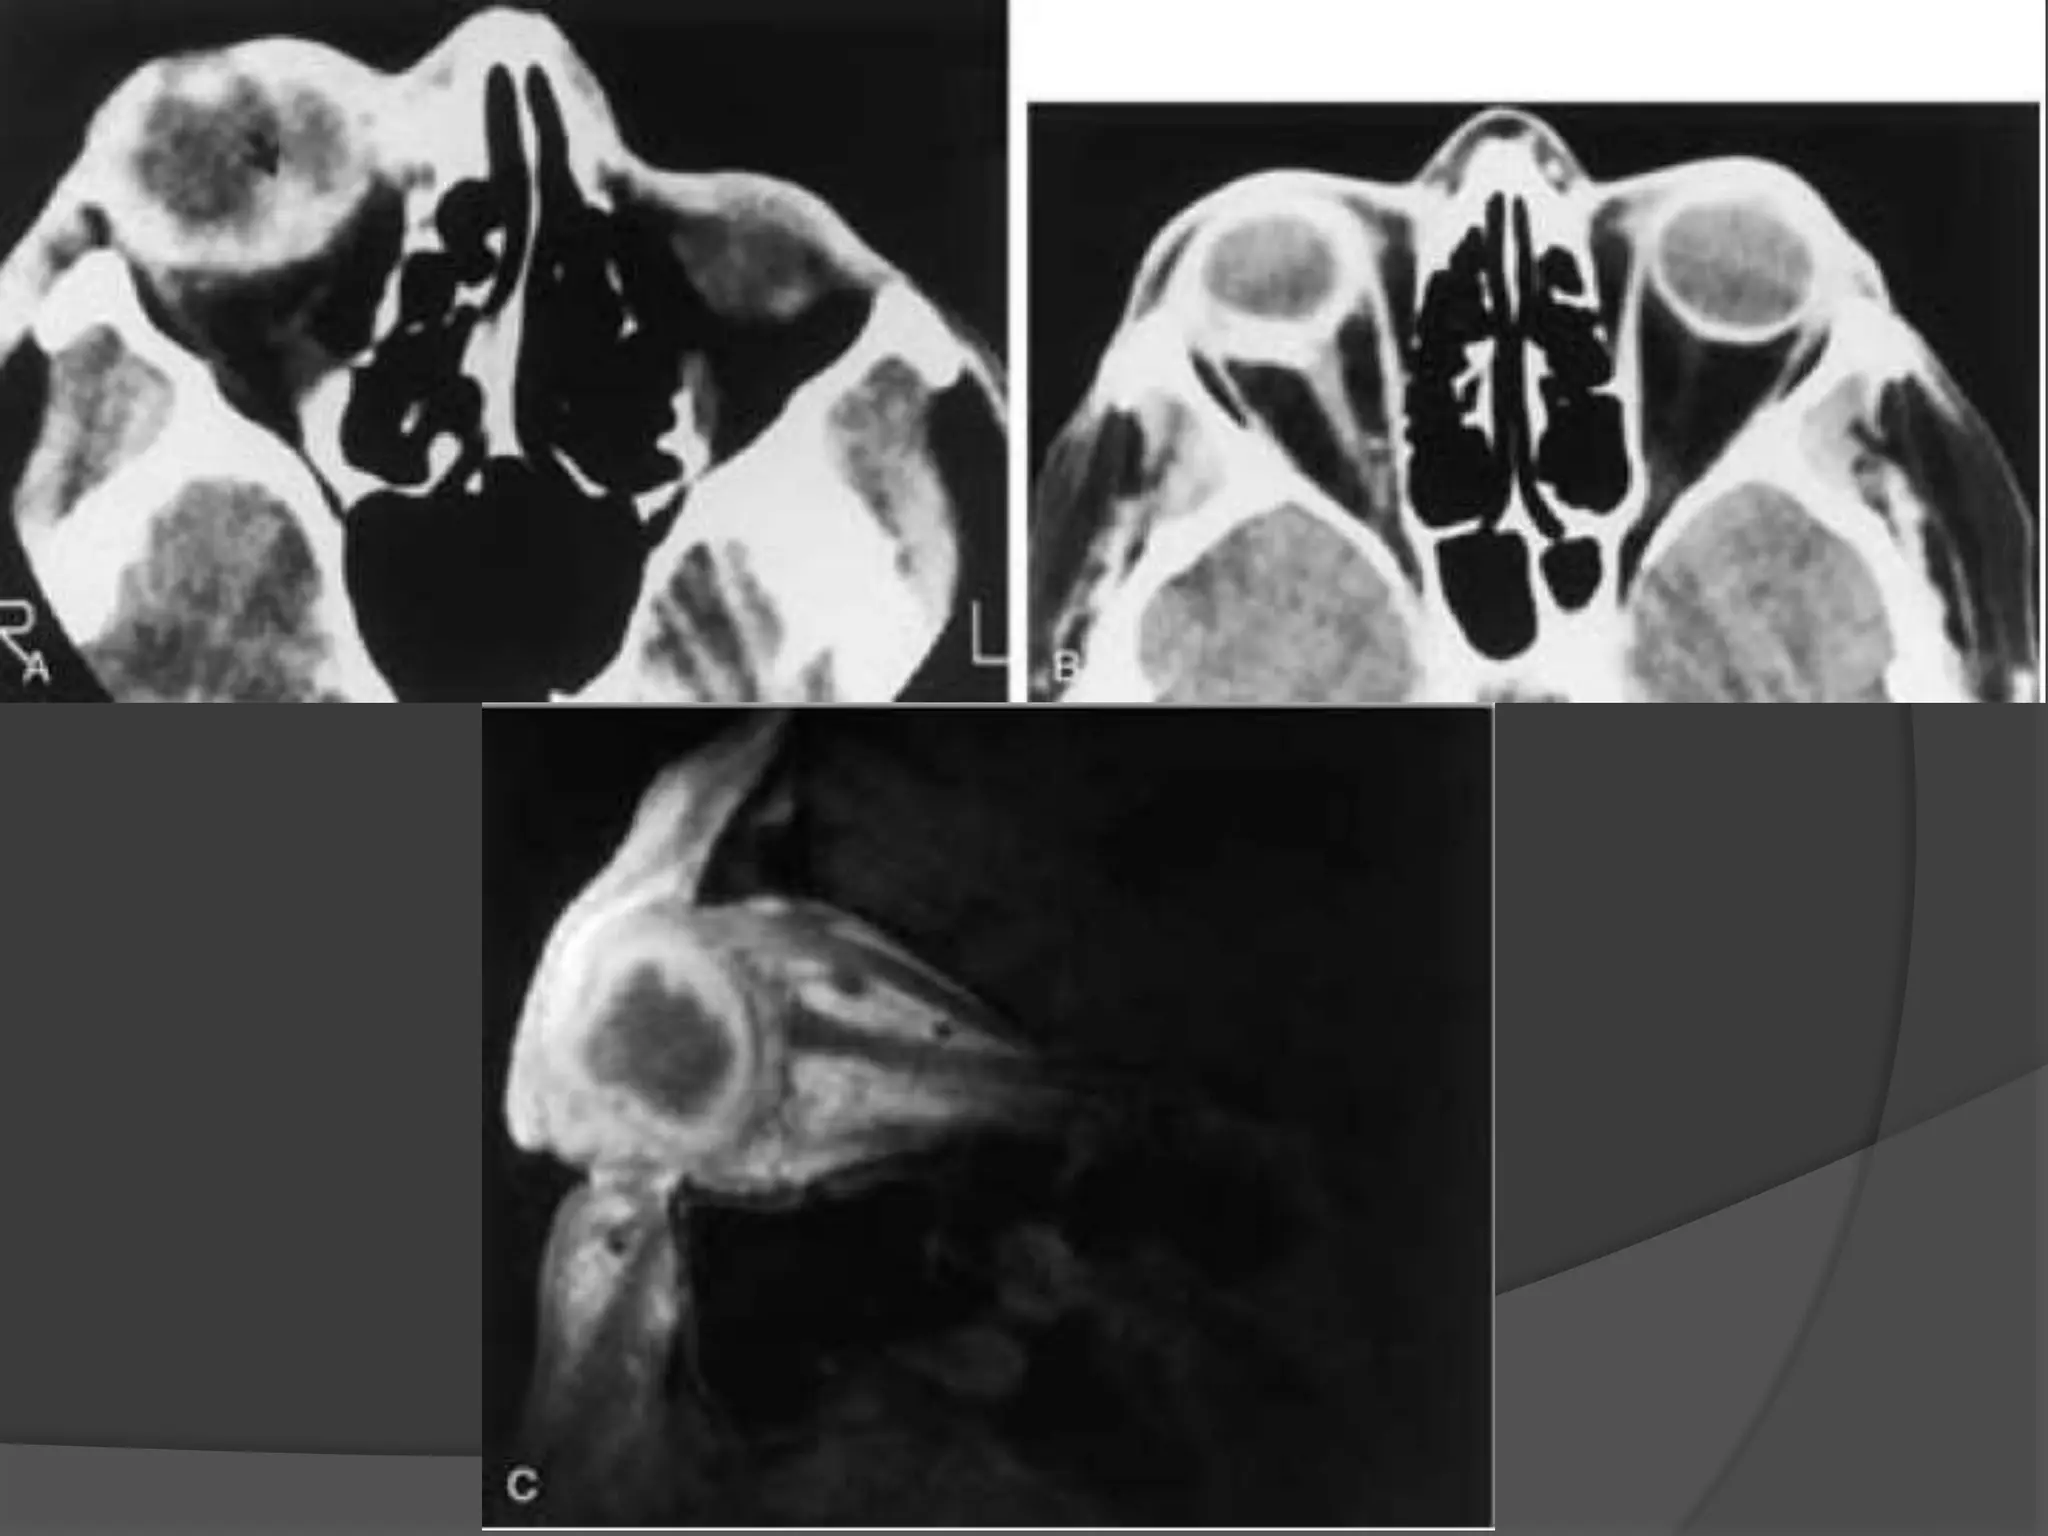

Rhabdomyosarcoma. CECT image

(A) Orbits demonstrates right proptosis due to large, lobular, intraorbital

mass.

(B) Image at lower level demonstrates invasion of right maxillary

sinus (asterisk) as well as extension through lateral orbital wall (arrow),

consistent with the aggressive nature of this tumor.

Rhabdomyosarcoma. CECT image (A)Orbits demonstrates right proptosis due to large, lobular, intraorbital mass. (B) Image at lower level demonstrates invasion of right maxillary sinus (asterisk) as well as extension through lateral orbital wall (arrow), consistent with the aggressive nature of this tumor.